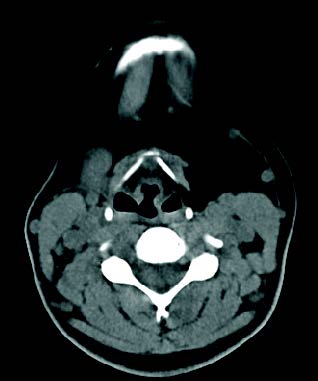

La PAAF de dicha tumoración se corresponde con tejido adiposo y en la TC cervical con contraste se visualiza una masa de estirpe grasa con dimensiones de nueve por cinco por un centímetro que se extiende desde la celda submaxilar hasta la musculatura omohiodea en sentido craneocaudal y desde la cara lateral del tiroides hasta la cara medial de la vena yugular interna (figura 2).

FIGURA 2: TC corte axial.